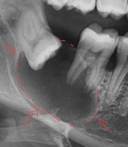

|

5 |

Quiste odontogénico |

Lesión

asintomática, de larga evolución, crecimiento lento y expansivo. Imagen

radiolúcida con bordes bien definidos y delgados.9 |

|||

6 |

Displasia cemento ósea periapical |

Lesión que presenta diferentes etapas dependiendo de su desarrollo. En su etapa inicial se observa como un área radiolúcida uní o multilocular bien delimitada. En etapas avanzadas se observa circunscrita con distintos grados de radiopacidad en su interior10 |

7 |

Granuloma |

Lesión periapical pequeña menor de 5mmm aproximadamente de forma redonda. Se observa una imagen radio lúcida de menor densidad que el quiste periapical.11 |

8 |

Hipercementosis |

Asintomático.

Se ve una cantidad excesiva de cemento a la largo de toda o par de la

superficie radicular. 11 |

9 |

Odontoma |

unilocular radiopaca, asintomática, con bordes definidos no corticalizados |

10 |

Folículo dentario hiperplásico |

Se observa un espacio radiolúcido homogéneo, alrededor de la corona de un diente en desarrollo y en dientes impactados se presenta como un ligera raciolucidez semicircular alrededor de los dientes no erupcionados.12 |